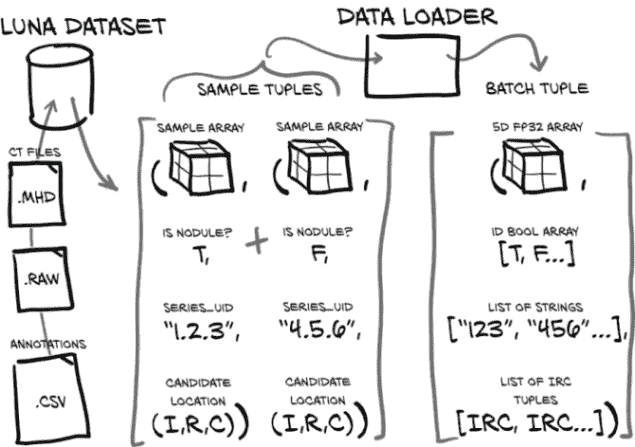

现在我们已经讨论了第二部分的高层目标,以及概述了数据将如何在我们的系统中流动,让我们具体了解一下这一章我们将要做什么。现在是时候为我们的原始数据实现基本的数据加载和数据处理例程了。基本上,你在工作中涉及的每个重要项目都需要类似于我们在这里介绍的内容。¹ 图 10.1 展示了我们项目的高层地图,来自第九章。我们将在本章的其余部分专注于第 1 步,数据加载。

图 10.1 我们端到端的肺癌检测项目,重点关注本章的主题:第 1 步,数据加载

我们的目标是能够根据我们的原始 CT 扫描数据和这些 CT 的注释列表生成一个训练样本。这听起来可能很简单,但在我们加载、处理和提取我们感兴趣的数据之前,需要发生很多事情。图 10.2 展示了我们需要做的工作,将我们的原始数据转换为训练样本。幸运的是,在上一章中,我们已经对我们的数据有了一些理解,但在这方面我们还有更多工作要做。

图 10.2 制作样本元组所需的数据转换。这些样本元组将作为我们模型训练例程的输入。

这是一个关键时刻,当我们开始将沉重的原始数据转变,如果不是成为黄金,至少也是我们的神经网络将会将其转变为黄金的材料。我们在第四章中首次讨论了这种转变的机制。

我们的Ct类将消耗这两个文件并生成 3D 数组,以及转换矩阵,将患者坐标系(我们将在第 10.6 节中更详细地讨论)转换为数组所需的索引、行、列坐标(这些坐标在图中显示为(I,R,C),在代码中用_irc变量后缀表示)。现在不要为所有这些细节担心;只需记住,在我们应用这些坐标到我们的 CT 数据之前,我们需要进行一些坐标系转换。我们将根据需要探讨细节。

我们还将加载 LUNA 提供的注释数据,这将为我们提供一个结节坐标列表,每个坐标都有一个恶性标志,以及相关 CT 扫描的系列 UID。通过将结节坐标与坐标系转换信息结合起来,我们得到了我们结节中心的体素的索引、行和列。

使用(I,R,C)坐标,我们可以裁剪我们的 CT 数据的一个小的 3D 切片作为我们模型的输入。除了这个 3D 样本数组,我们必须构建我们的训练样本元组的其余部分,其中将包括样本数组、结节状态标志、系列 UID 以及该样本在结节候选 CT 列表中的索引。这个样本元组正是 PyTorch 从我们的Dataset子类中期望的,并代表了我们从原始原始数据到 PyTorch 张量的标准结构的桥梁的最后部分。

11.3.2 数据加载器的照料和喂养

我们在上一章中构建的LunaDataset类充当着我们拥有的任何“荒野数据”与 PyTorch 构建模块期望的更加结构化的张量世界之间的桥梁。例如,torch.nn.Conv3d ( pytorch.org/docs/stable/nn.html#conv3d) 期望五维输入:(N, C, D, H, W):样本数量,每个样本的通道数,深度,高度和宽度。这与我们的 CT 提供的本机 3D 非常不同!

您可能还记得上一章中LunaDataset.__getitem__中的ct_t.unsqueeze(0)调用;它提供了第四维,即我们数据的“通道”。回想一下第四章,RGB 图像有三个通道,分别用于红色、绿色和蓝色。天文数据可能有几十个通道,每个通道代表电磁波谱的各个切片–伽马射线、X 射线、紫外线、可见光、红外线、微波和/或无线电波。由于 CT 扫描是单一强度的,我们的通道维度只有大小 1。

还要回顾第 1 部分,一次训练单个样本通常是对计算资源的低效利用,因为大多数处理平台能够进行更多的并行计算,而模型处理单个训练或验证样本所需的计算量要少。解决方案是将样本元组组合成批元组,如图 11.4 所示,允许同时处理多个样本。第五维度(N)区分了同一批中的多个样本。

图 11.4 将样本元组整合到数据加载器中的单个批元组中

方便的是,我们不必实现任何批处理:PyTorch 的DataLoader类将处理所有的整理工作。我们已经通过LunaDataset类将 CT 扫描转换为 PyTorch 张量,所以唯一剩下的就是将我们的数据集插入数据加载器中。